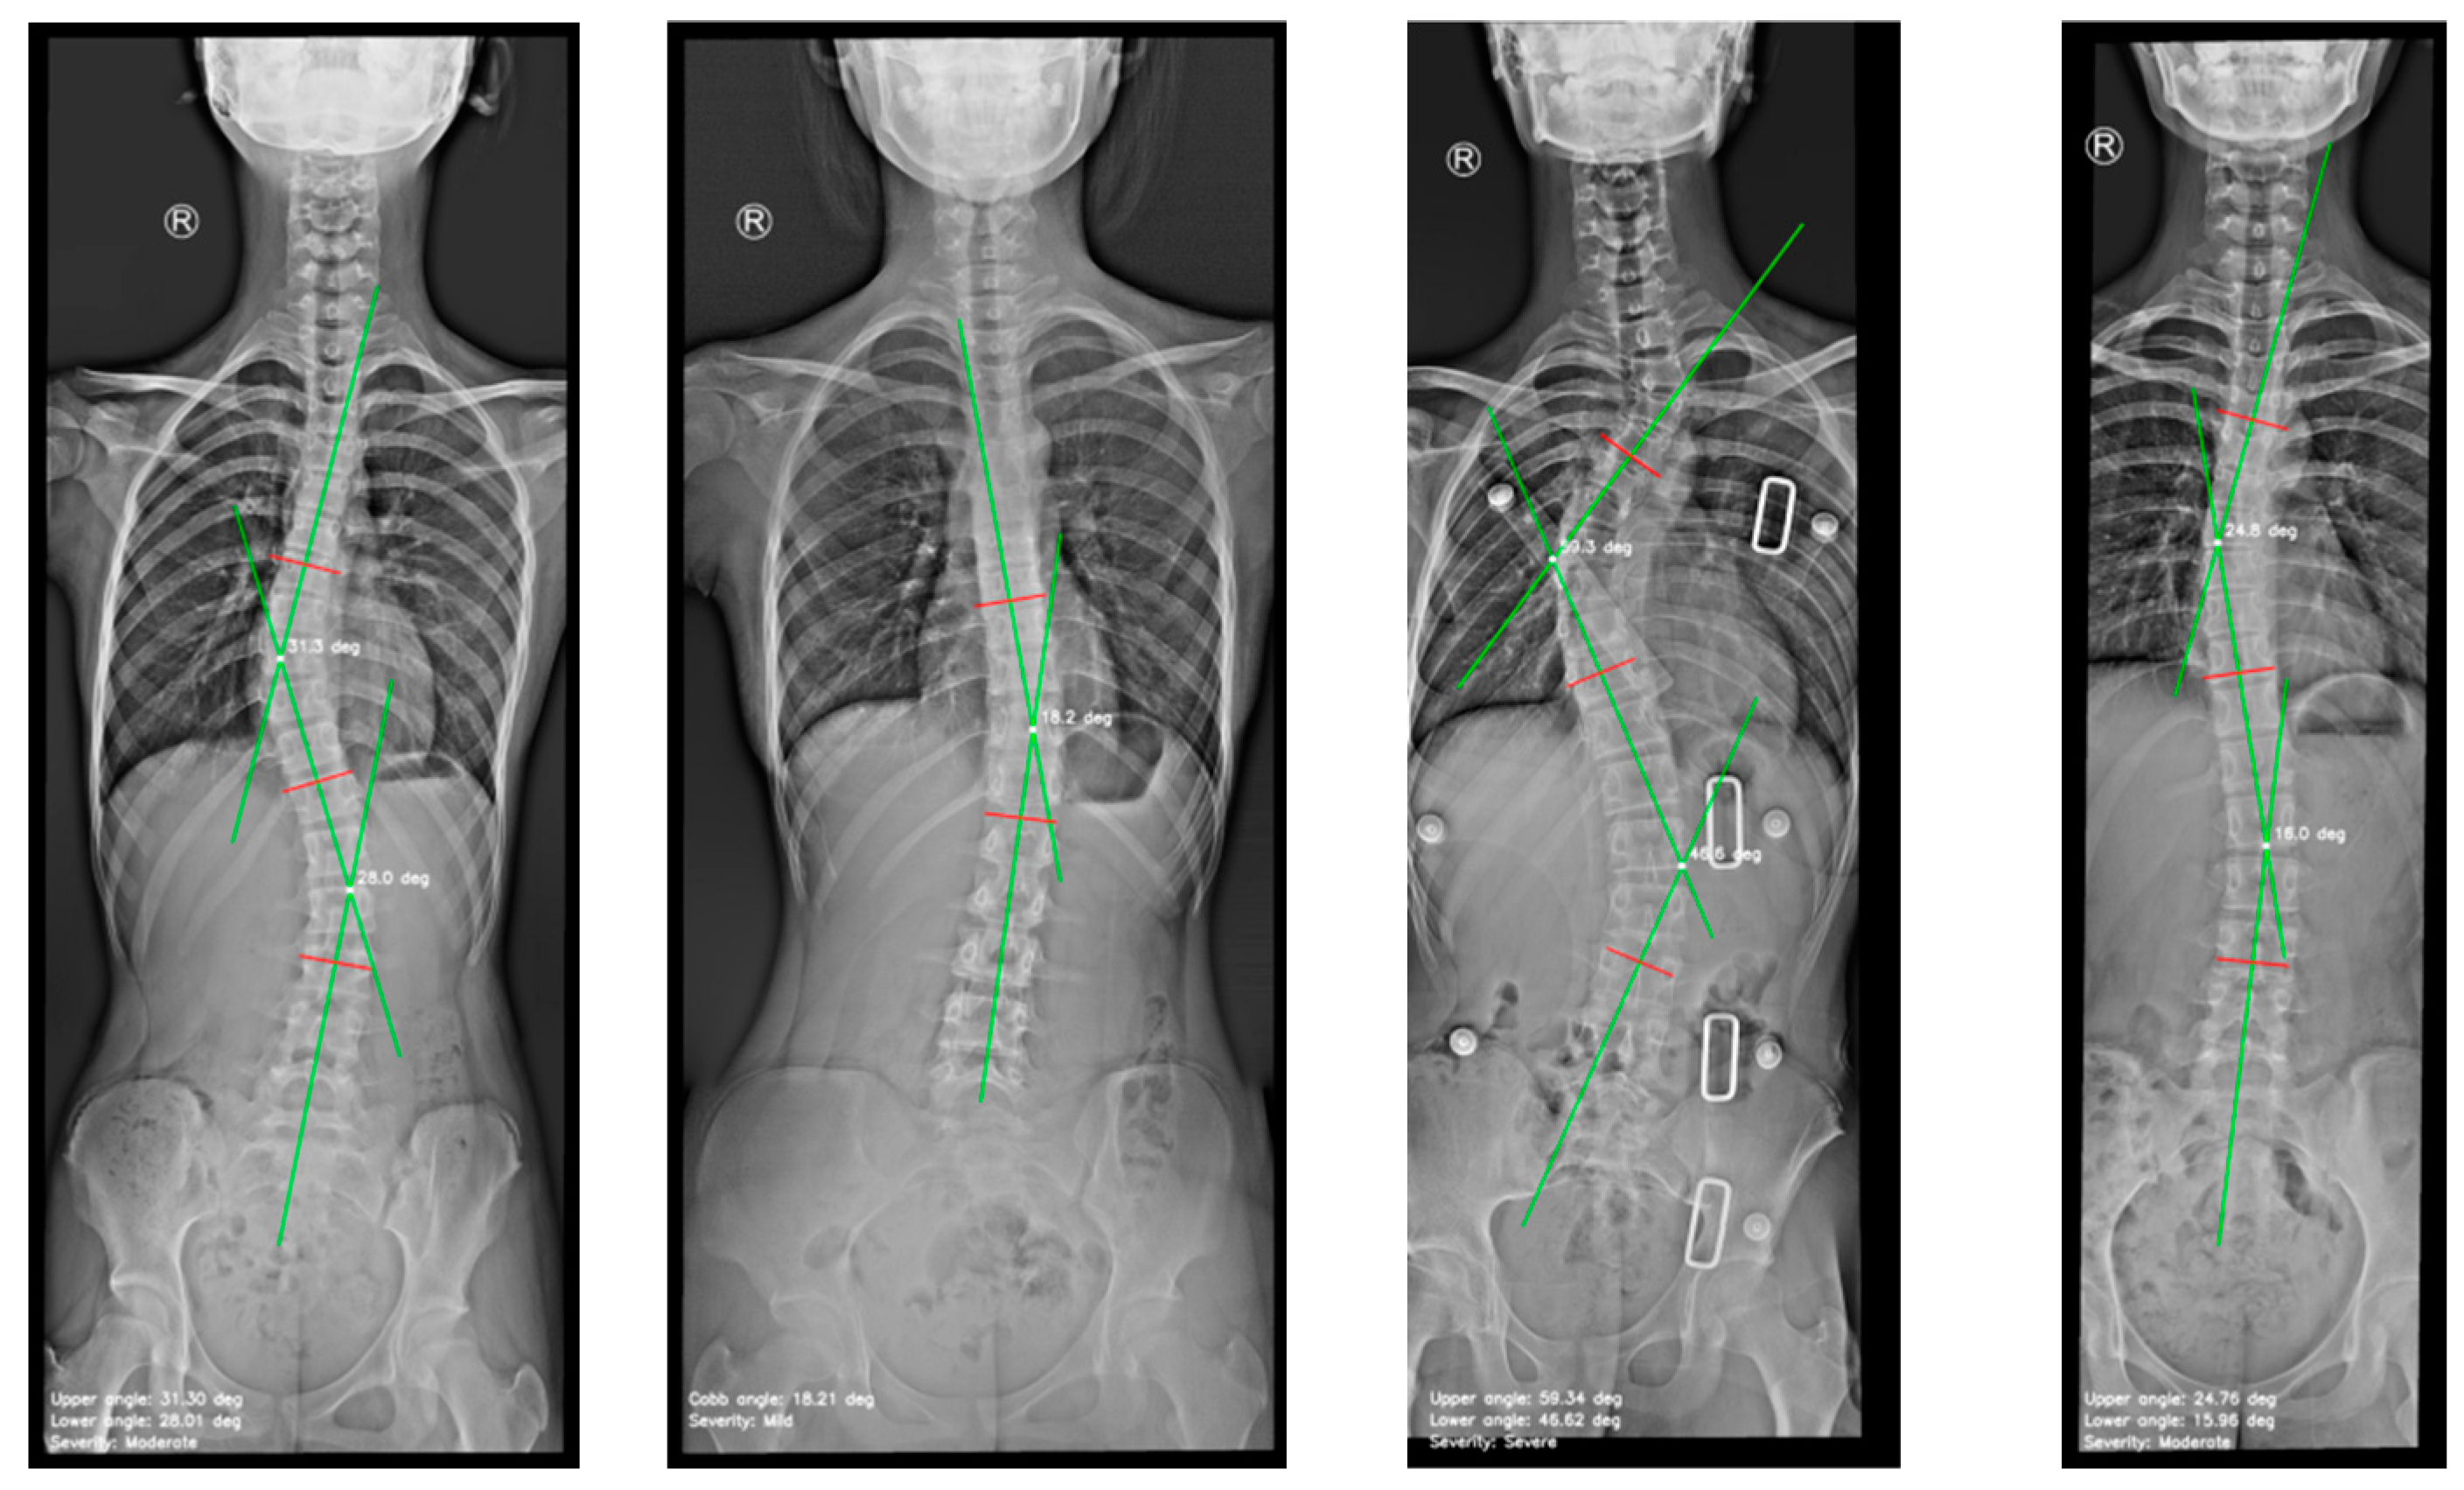

- Figure 6(d), depicts spinal curve estimation and Cobb angle calculation. In this step, the extracted midpoints are used to approximate the spinal curve, with the first and last midpoints identified as upper and lower, respectively. A spline interpolation is applied to refine the connections between midpoints, providing a more accurate approximation of the spinal curvature. At each midpoint, except for upper and lower, a perpendicular line is drawn relative to the tangent of the curve at that point. The inclination angle of these perpendicular lines with respect to the horizontal is then computed and annotated on the corresponding midpoints. These perpendicular lines, referred to as simplified vertebrae, allow for a visual assessment of the spinal curvature trend, facilitating an intuitive evaluation of scoliosis progression and severity. Based on the curvature analysis, key anatomical landmarks are identified, including tilted vertebrae and apex points. Tilted vertebrae are defined as those with the most pronounced inclination angles, representing the regions of greatest spinal deviation. Apex points, on the other hand, correspond to the locations where the spinal curve reaches its maximum deformation, characterised by the greatest lateral displacement relative to the upper reference point. These apex points are critical for scoliosis assessment, as they indicate the peak of the spinal misalignment. The Cobb angle is then computed by isolating perpendicular lines corresponding to the most tilted vertebrae, drawing representative lines that emulate the manual method, identifying the intersection point between these lines, and measuring the angle formed at their intersection.

- Finally, the visualization and data export stage is presented in Figure 6(e). The results are displayed in a multi-panel layout including: the original X-ray image; the segmentation mask; the extracted spinal contour with the computed midpoints, midline, and vertebral inclination; the image showing Cobb angle measurement and severity classification; and finally, the data table containing numerical values including anatomical landmarks such as tilted vertebrae, upper, lower and apex points. Processed images and the data table are exported as structured reports in .png and .csv formats, providing a comprehensive representation of the entire process. This facilitates data-driven monitoring and assessment of scoliosis progression, offering valuable insights for clinical experts.

4.2. Cobb Angle Measurement